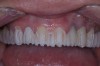

Figure 3  Preoperative view. Note the worn incisal edges and end-on-end occlusal relationship requiring an increase in OVD to restore.

Figure 3